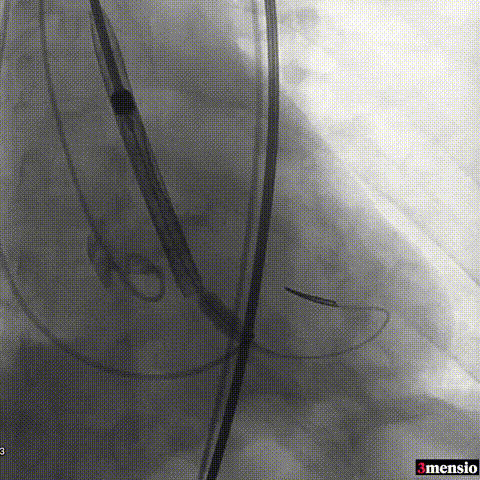

图片

主动脉根部造影

导丝跨瓣

22mm球囊预扩